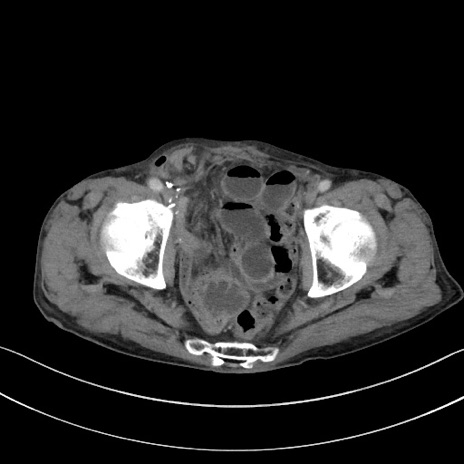

症例3(横断像)

【症例】 70歳代男性

【主訴】右鼠径部腫瘤、疼痛

【現病歴】本日朝より上記主訴あり、受診。

【既往歴】膀胱癌にて膀胱全摘、両側尿管皮膚瘻

【データ】WBC 5600、CRP 0.56